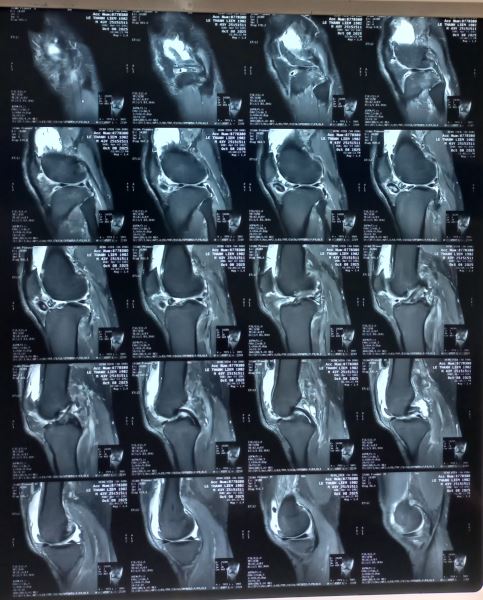

Chúng tôi nghĩ đến bệnh Synovial Osteochondromatosis một loại bệnh hiếm gặp và cho bệnh chân chụp MRI khớp cho kết quả sau:

Bệnh nhân khác